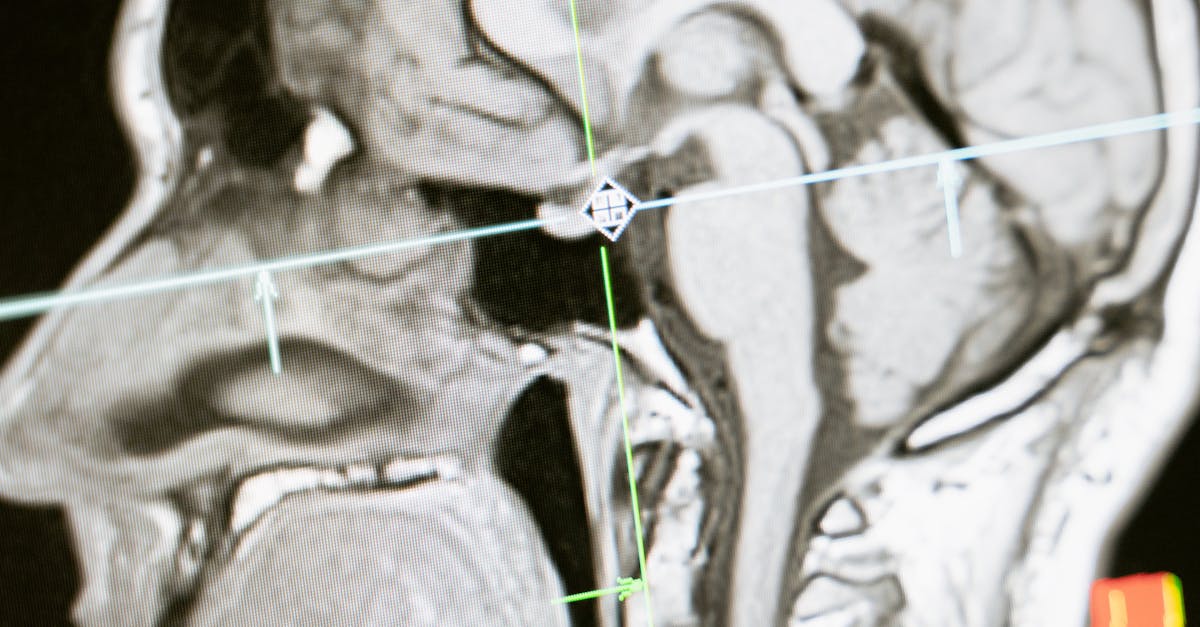

En cas de doute, des examens complémentaires peuvent être nécessaires. Ces examens permettent d’approfondir le diagnostic et d’identifier d’éventuelles pathologies sous-jacentes. Ils incluent des bilans biologiques et des imageries médicales comme la radiographie, l’échographie, ou l’IRM. Chacun de ces outils contribue à fournir une image claire et précise de la situation clinique du patient.

Parallèlement, des imageries médicales telles que la radiographie, l’IRM ou l’échographie peuvent être prescrites. Ces examens permettent d’obtenir des images détaillées de la colonne vertébrale et des tissus environnants, contribuant ainsi à une évaluation plus complète de la situation.

La troisième étape, bien qu’elle soit facultative, concerne les examens complémentaires. Lorsque le praticien estime qu’un diagnostic n’est pas encore clair après l’anamnèse et l’examen physique, il peut recommander des examens complémentaires. Cela inclut des bilans biologiques, mais également de l’imagerie médicale comme des radiographies, des échographies, et des IRM pour visualiser l’état des structures internes et identifier des lésions ou des anomalies.

Enfin, les examens complémentaires représentent une troisième phase qui permet de valider ou de compléter le diagnostic initial. Si les résultats de l’anamnèse et de l’examen physique laissent des zones d’ombre, des bilans biologiques ou des études d’imagerie médicale telles que l’IRM ou la radiographie pourront être prescrits. Ces procédures apportent des données supplémentaires et représentent un outil précieux pour un diagnostic approfondi.